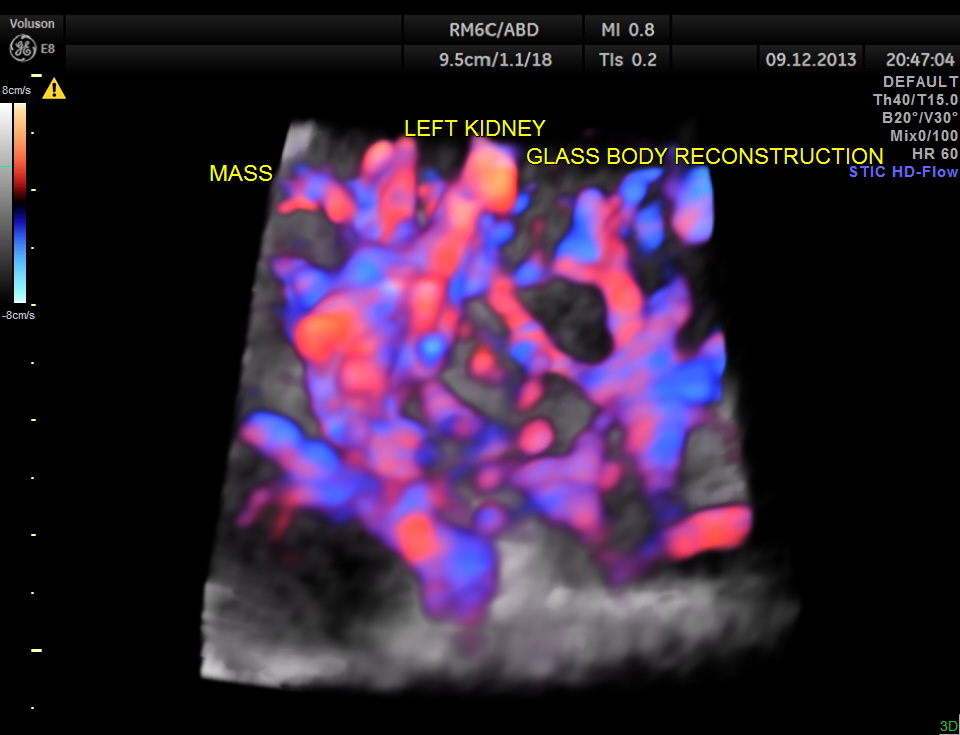

COLOUR FLOW ONLY RECONSTRUCTION.